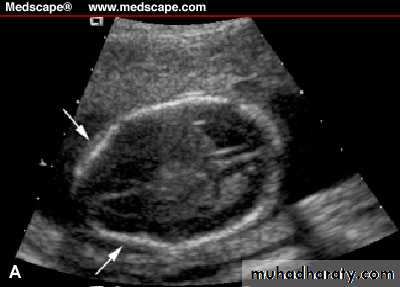

Neural tube defects:Anencephaly&encephalocele can be detected on first trimester U/S

Spina bifida:’lemon’&’banana’sign